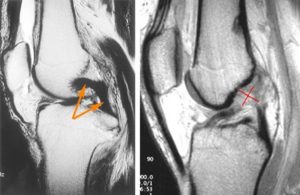

МРТ – наиболее достоверный современный метод томографии, с его помощью можно определить любые изменения в тканях сустава, их размер и локализацию с высокой степенью точности.

Любая травма колена является показанием к рентгенографии. При этом невозможно увидеть связки, так как на рентгенограмме отображаются лишь костные ткани. Однако рентген позволяет исключить ряд патологий, связанных с деформацией костей. УЗИ при разрыве связок не назначают. Наиболее информативным методом диагностики при подозрении на повреждение КС является МРТ.

Магнитно-резонансная томография считается наиболее информативным и точным методом диагностики. При травмировании она указывает на ангуляцию связки – сгибание, нехарактерное для нормального положения.

В то же время ангуляцию можно рассмотреть и с помощью узи. При чем, этот метод будет дешевле и менее вредным для здоровья.